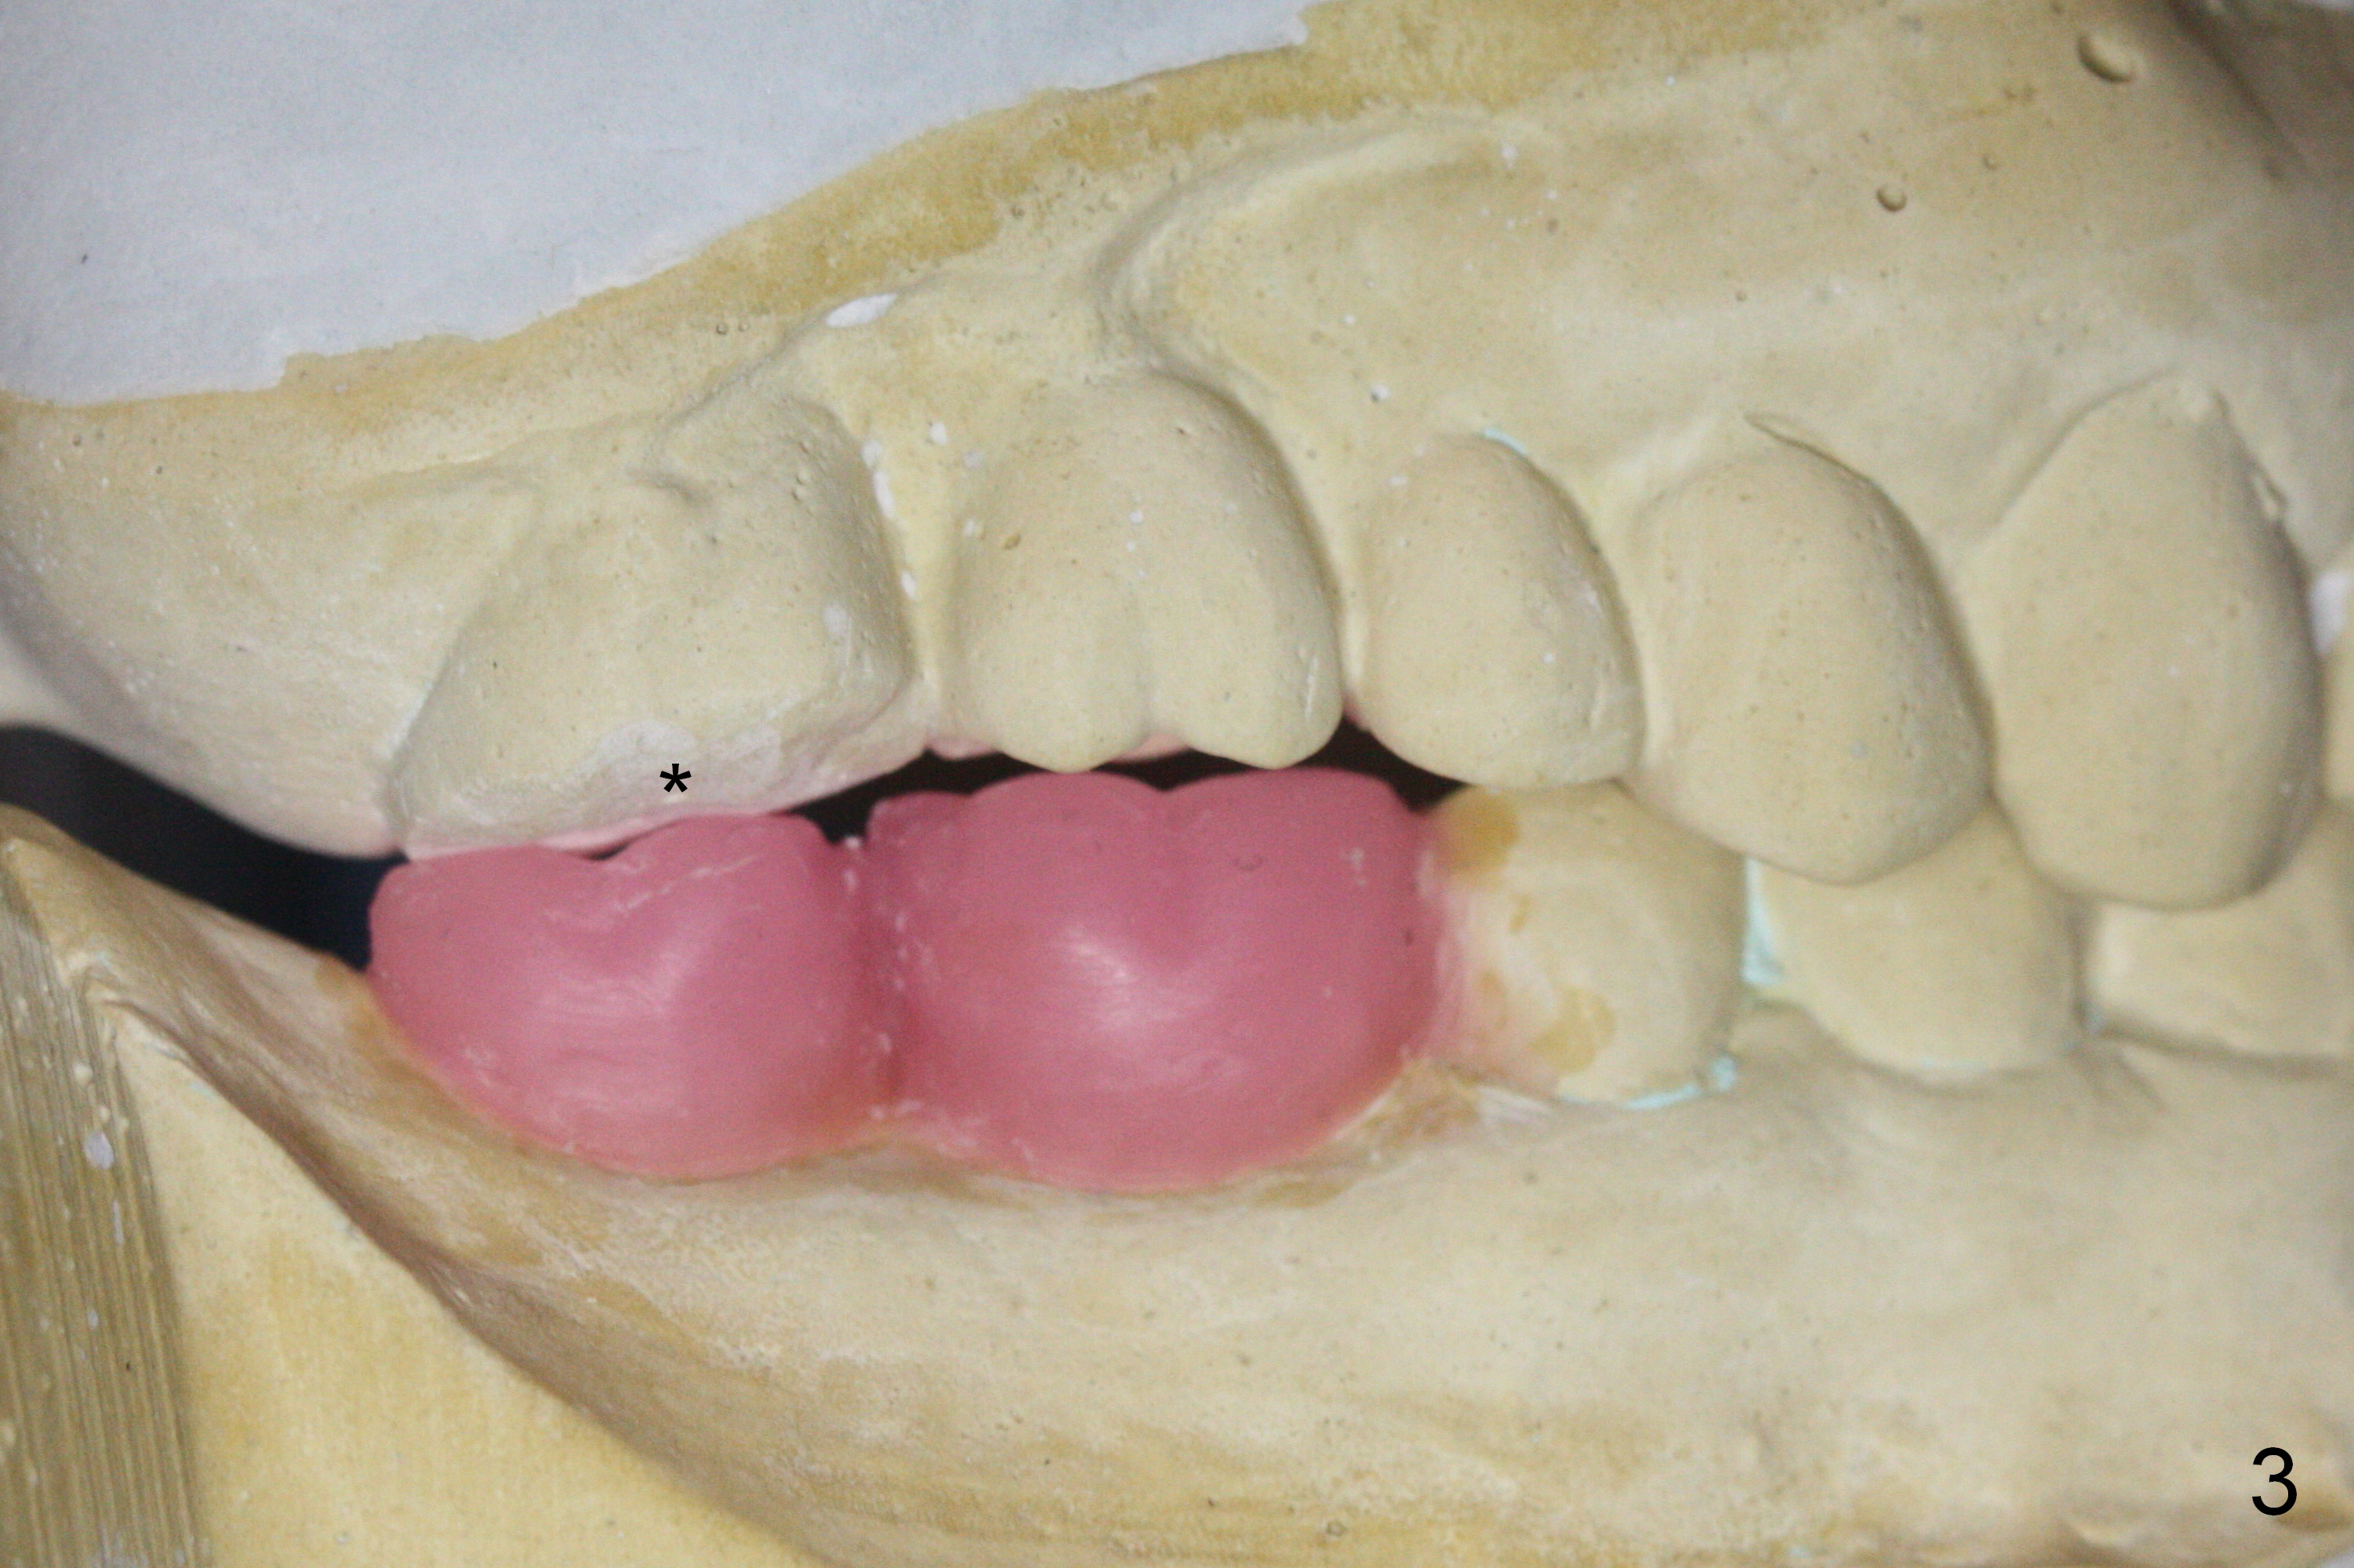

A 54-year-old man has multiple restoration (Fig.1). The curve of Spree on the right side is abnormal (arrow with #2 supraocclusal; #3 and 4 infraocclusal). Bone density at the sites of #30 and 31 appears to be low. Prepare bone expansion.